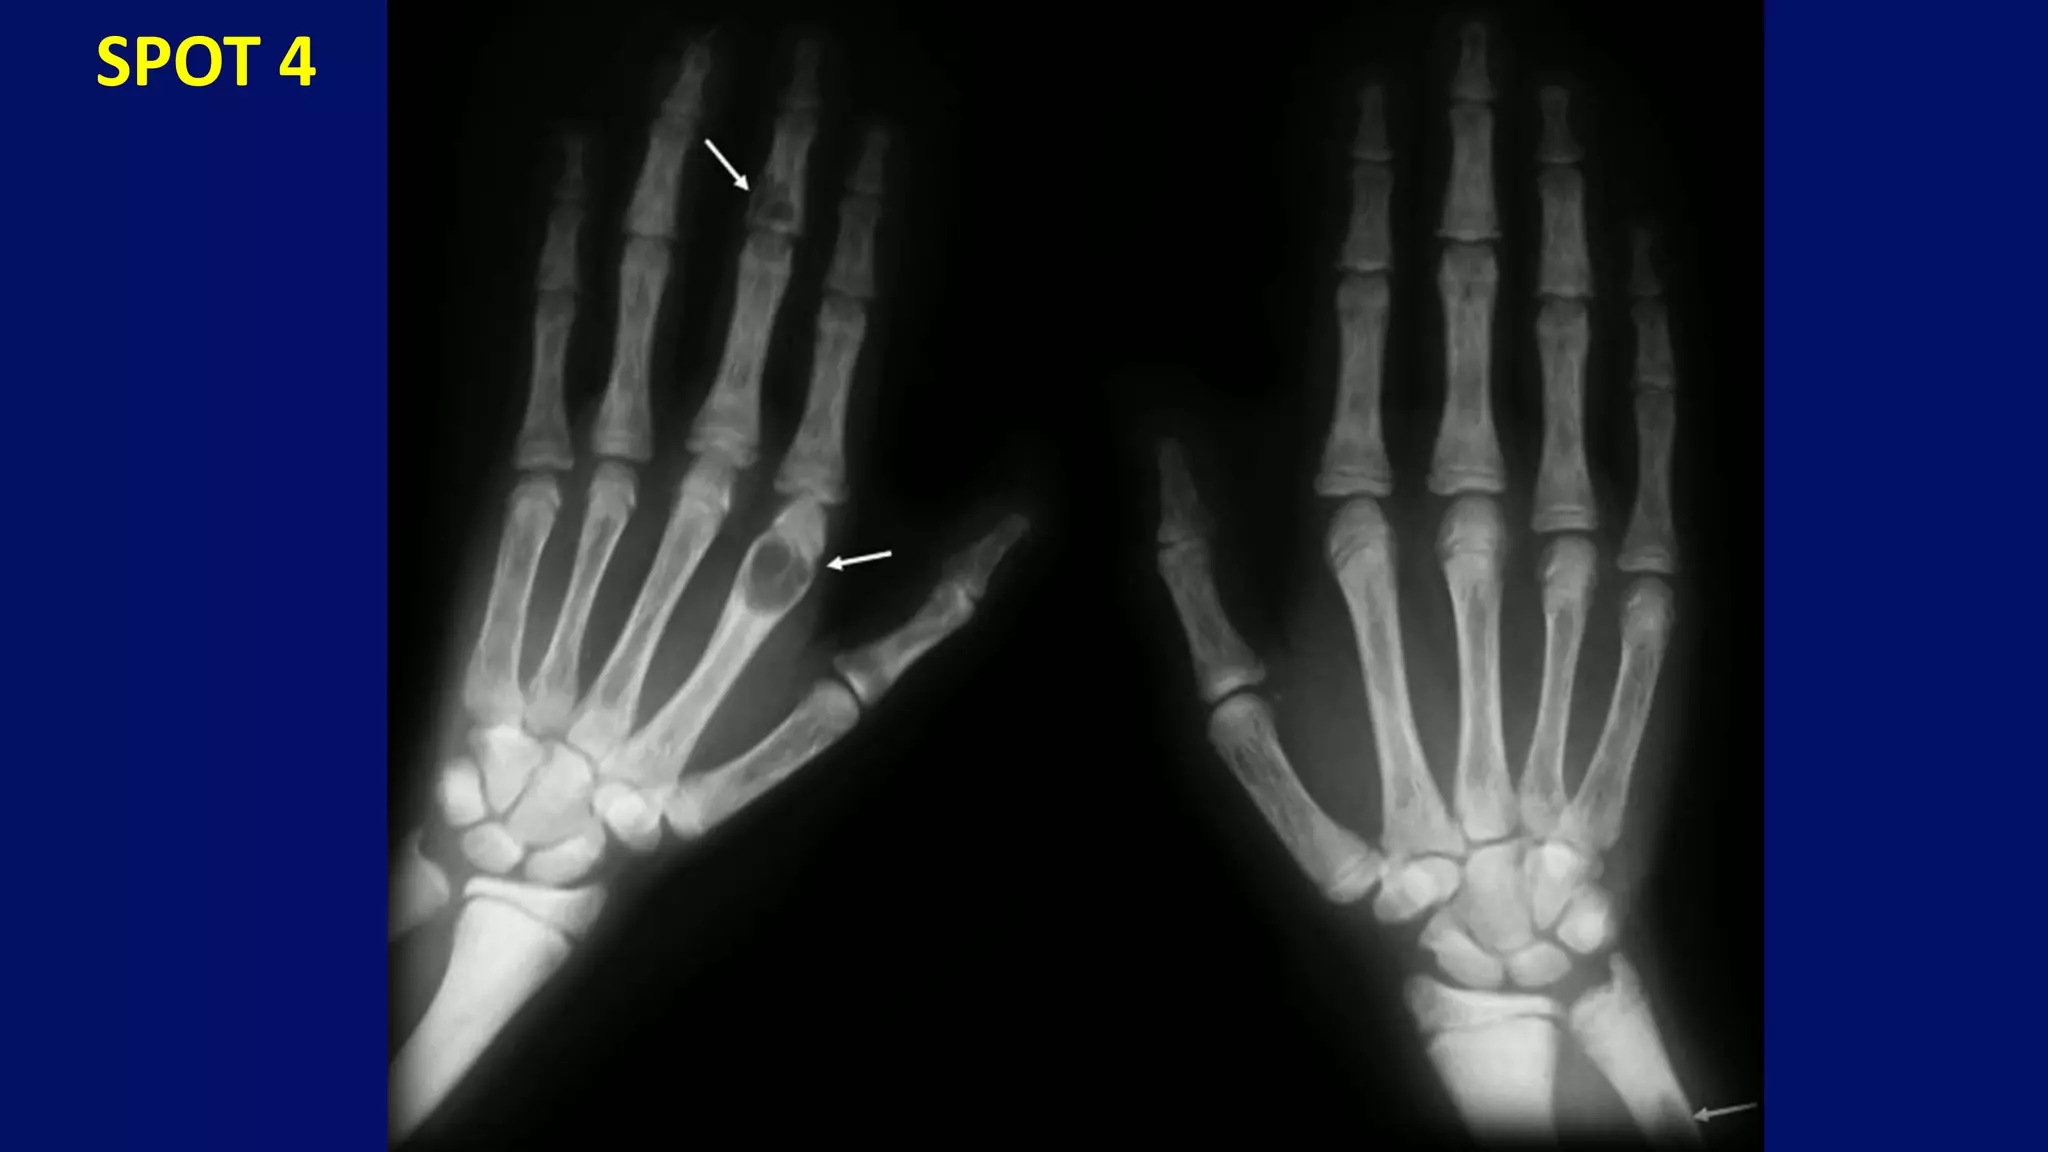

• Tuft resorption and DIP erosions

(Scleroderma)

• Erosive arthritis (Rheumatoid arthritis)

• Deforming, nonerosive arthritis (SLE)

Abnormal tapering of the distal soft tissues

and early surface erosion of the phalangeal

condyle.

Subtle surface erosions and Progressive erosions

Terminal tuft resorption

Subluxation of IP joint of the thumb and advanced ulnar deviation

• #86 Moderate juxta-articular demineralization associated with periarticular soft-tissue swelling and abnormal tapering of the distal soft tissues (A). Close-up view of proximal interphalangeal joint of this patient (8) demonstrates capsular distension and early surface erosion of the phalangeal condyle (arrows).

• #87 Subtle surface erosions (closed arrows) of the metacarpal head and base of proximal phalanx simulating early rheumatoid arthritis (A). In (8) and (C) progressive erosions (open arrows) of the proximal interphalangeal joint can be seen occurring over a 21-month period.

• #88 Subtle surface erosions (closed arrows) of the metacarpal head and base of proximal phalanx simulating early rheumatoid arthritis (A). In (8) and (C) progressive erosions (open arrows) of the proximal interphalangeal joint can be seen occurring over a 21-month period.

• #89 subluxation of interphalangeal joint of the thumb and advanced ulnar deviation with subluxation of the second through fifth metacarpophalangeal joints